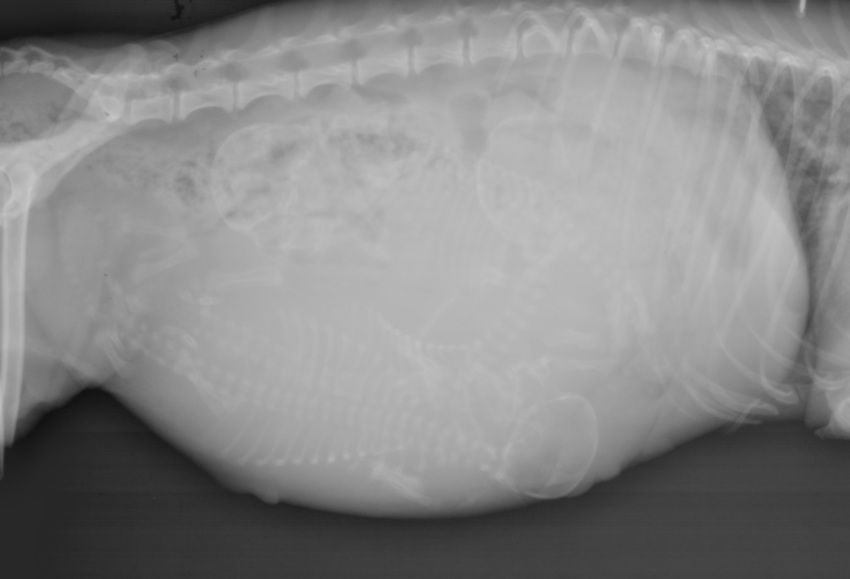

Na de rontgen zei de DA 3, sommigen hier zien er 4. Wat zien jullie? Ik word er gek van, en ga morgen toch de DA weer bellen.

Maar voor de puzzelaars onder ons, wat zien jullie?

Ik denk er 4 te zien, kijk maar eens naar de onderste ruggengraat en het lijkt net alsof daar nog eentje naast loopt en twee set achterpoten bij de vulva.

Schedeltje net onder de andere. ????

Rontgen zou bij kleine nesten toch uitsluitsel geven over het aantal te verwachten pups. ???????

Ja, lijkt er inderdaad wel op. Ik denk niet dat zoiets een uitsluitsel kan geven. Je kan nou immers niet alles zien omdat de ruimte beperkt is en de pups dicht op elkaar zitten.

Nou, Ruby, de DA wilde graag een rontgen om zeker te weten hoeveel pups het zouden zijn, hij heeft mij overgehaald. Dan zouden we weten wanneer ze klaar is met bevallen. En omdat de echo niet alles goed weer kan geven, maar dat is bekend. Wat we zagen was levendig. Dus rontgen om uitsluitsel te verkrijgen, mijn eerste rontgen en dan zie ik meer?

Drie, maar als je da de belichting iets aanpast, kun je de schedels beter zien. Bij digitale Rx is dat erg handig. Dan weet je het zeker.

Mijn man heeft de belichting iets aangepast en echt een schedeltje is het meest lastige om te zien.

Via het programma wat bij de digitale rontgen hoort kun je echt makkelijk de foto zó aanpassen dat de schedels echt goed te zien zijn. Dat kun je niet op een normale pc. Waarschijnlijk heeft jouw da dus duidelijker gezien (dan wij nu) dat het er drie zijn.

Nou de DA riep eigenlijk meteen 2 omdat met de echo 2 te zien waren. Ik zei: ik voel echt drie, eentje onder haar ribben en de assistente zag het toen ook, en toen werden het er 3.

Het gaat te ver om uit te leggen waarom we op dag 60 echo en rontgen lieten doen, Mar was echt zeer grondig onderbouwt. Niet elke papillon bevalt zonder problemen, kleine nesten, grote pups, vaker calcium tekort met weeenzwakte en dan blijft de laatste pup achter, etc. Redenen zat en tot nu toe altijd mijn eigen ‘handen’ vertrouwt.

De pups zijn erg groot! Ik weet nu dat ik niet onnodig moet wachten. Alles is gedocumenteerd om welzijn van moeder en pups te waarborgen, voor zover wij dat kunnen.

Ik zie er duidelijk drie. Drie duidelijke schedels met ruggengraten daar aan. Ik snap wat je bedoelt met dat dubbele ruggengraatje/schedeltje, maar ik vind het niet duidelijk genoeg om te zeggen "dat is een pup", dus ik zou het voor nu houden op 3 met kans op verrassingen. ;)

Voor mij zijn het drie, tamelijk grote zelfs, pups.

Ik vind de foto wel niet zo goed genomen.